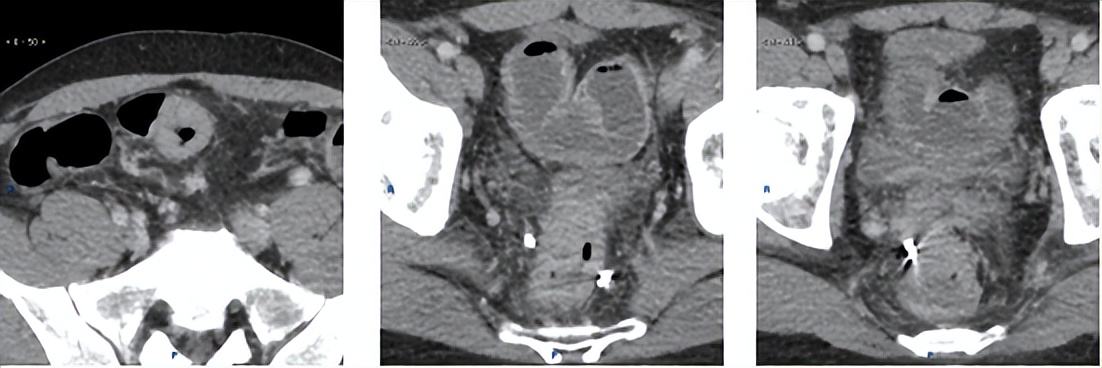

2017.11超声和CT

腹部超声:肝内多发性占位病变性质待查,结合病史考虑转移性肝癌可能,其它疾患待排,建议超声造影。

胸腹部增强CT:1.“右半结肠癌术后”,吻合口远侧复发肠癌,CT分期 rT3N0M1a;2.肝S3、S6病变,结合病史,考虑转移。

▲上:2016.12.21;下:2017.11.14。